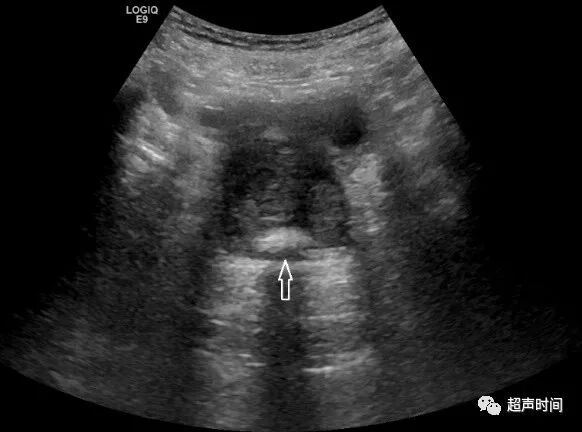

为避免误解,对只在尿道内的强回声才称为结石,前列腺实质内的强回声称为钙化(图 1)。

图 1 经腹部超声显示前列腺钙化。患者 80 岁,前列腺体积 54 cm³,中叶突向膀胱,外周带变薄,外科包膜处钙化(箭头示)

超声检查时,在前列腺中后份有多颗大小不等的点状强回声,大小约 1~3 mm,很少有超过 10 mm 的钙化。

前列腺这一钙化带是内外腺的分界,也是外科包膜的标志。前列腺钙化表示良性增生(图 2),前列腺癌少有钙化。

图 2 前列腺增生伴钙化。前列腺体积 62 cm³,外科包膜多发钙化(箭头),外周带变薄,中央区和移行区增大,精囊腺厚 1.2 cm(测量标志)